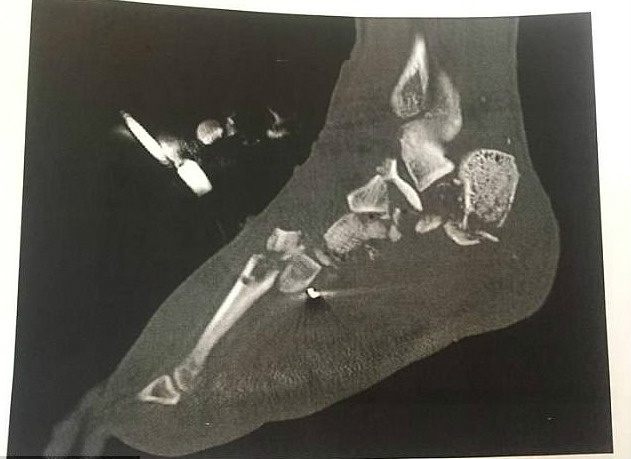

ਵਾਸ਼ਿੰਗਟਨ— ਅਮਰੀਕਾ 'ਚ ਰਹਿਣ ਵਾਲੇ ਇਕ ਸ਼ਖਸ ਨੇ ਰੈਡਿਟ 'ਤੇ ਹੈਰਾਨ ਕਰਨ ਵਾਲਾ ਖੁਲਾਸਾ ਕੀਤਾ ਹੈ। IncrediblyShinyShart ਨਾਂ ਦੇ ਰੈਡਿਟ ਯੂਜ਼ਰ ਦਾ ਕਹਿਣਾ ਹੈ ਕਿ ਉਸ ਨੇ ਆਪਣੇ ਪੈਰ ਦਾ ਮਾਸ ਆਪਣੇ ਦੋਸਤਾਂ ਨੂੰ ਪਕਾ ਕੇ ਖਿਲਾਇਆ ਤੇ ਖੁਦ ਵੀ ਇਸ ਦਾ ਸੁਆਦ ਲਿਆ। ਡੇਲੀ ਮੇਲ ਦੀ ਰਿਪੋਰਟ ਮੁਤਾਬਕ 2 ਸਾਲ ਪਹਿਲਾਂ ਸੜਕ ਹਾਦਸੇ 'ਚ ਉਸ ਦਾ ਪੈਰ ਬੂਰੀ ਤਰ੍ਹਾਂ ਖਰਾਬ ਹੋ ਗਿਆ ਸੀ। ਪੂਰੇ ਸਰੀਰ ਨੂੰ ਇੰਫੈਕਸ਼ਨ ਤੋਂ ਬਚਾਉਣ ਲਈ ਆਪਰੇਸ਼ਨ ਕਰਕੇ ਪੈਰ ਨੂੰ ਵੱਢਣਾ ਪਿਆ।

ਆਪਰੇਸ਼ਨ ਤੋਂ ਬਾਅਦ ਵਿਅਕਤੀ ਨੇ ਡਾਕਟਰ ਤੋਂ ਆਪਣਾ ਪੈਰ ਮੰਗ ਲਿਆ ਸੀ। ਹਸਪਤਾਲ ਤੋਂ ਡਿਸਚਾਰਜ ਹੋਣ ਤੋਂ ਬਾਅਦ ਸਟਾਫ ਨੇ ਵਿਅਕਤੀ ਨੂੰ ਬਾਇਓਬੈਗ 'ਚ ਭਰ ਕੇ ਉਸ ਦਾ ਕੱਟਿਆ ਪੈਰ ਵੀ ਦੇ ਦਿੱਤਾ। ਵਿਅਕਤੀ ਨੇ ਆਪਣਾ ਪੈਰ ਲਿਆ ਕੇ ਫ੍ਰਿਜ਼ 'ਚ ਰੱਖ ਦਿੱਤਾ। ਤਿੰਨ ਹਫਤੇ ਬਾਅਦ ਉਸ ਨੂੰ ਆਪਣਾ ਪੈਰ ਪਕਾ ਕੇ ਖਾਣ ਦਾ ਖਿਆਲ ਆਇਆ। ਉਸ ਨੇ ਆਪਣੇ 11 ਦੋਸਤਾਂ ਨੂੰ ਫੋਨ ਕੀਤਾ ਤੇ ਪੁੱਛਿਆ ਕਿ ਕੀ ਉਹ ਕਾਨੂੰਨੀ ਤੌਰ 'ਤੇ ਮਨੁੱਖੀ ਮਾਸ ਦਾ ਸੁਆਦ ਲੈਣਾ ਚਾਹੁੰਦੇ ਹਨ? ਇਸ 'ਤੇ ਸਾਰੇ ਦੋਸਤ ਦਾਵਤ ਲਈ ਤਿਆਰ ਹੋ ਗਏ।